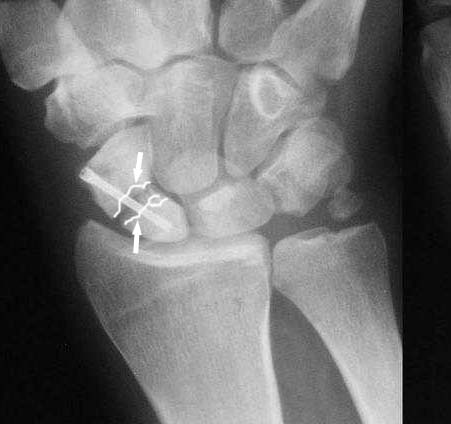

I am not sure if the differential of a nonunion vs. pseudoarthrosis means much in this context. The distal pole of the screw has a lucency, so the

nonunion is most likely unstable and moving. It needs revision. The radial styloid does not have evidence of DJD, so I do not think it needs to be resected. The surgery will probably require an open revision, removal of necrotic bone and soft tissue interposition, and would benefit from some

>>Здаётся мне Вы имеете удовольствие видеть ложный сустав ладьевидной кости.

Такое ощущение, что имеющееся состояние ещё не является необратимым (отсутствие склероза отломков на уровне перелома) и обусловлено исключительно нестабильностью (сам винт оказался слабоват или чрезмерные нагрузки привели к срыву фиксации - пациент, заметьте, мотоциклист!)

Ув. Данил! По моему мнению все-таки ложный сустав -склероз отломков (приложение), 5 мес, диастаз. Для подтверждения можно выполнить КТ кистевого сустава (формирование замыкательной пластинки, склероз концов отломков и т.д.,), а так же по КТ можно выявить сохраняется ли подвывих каких-либо костей запястья или нет. При наличии ложного сустава целесообразно будет удалить винт,обработать концы отломков, разрушив замыкательные пластинки и выполнить остеосинтез ладьевидной кости винтом с костной аутопластикой зоны псевдоартроза (либо гидроксиаппатитом...) Гипс 1,5 мес мин. Снимков найти сейчас не получилось. позже дошлю.